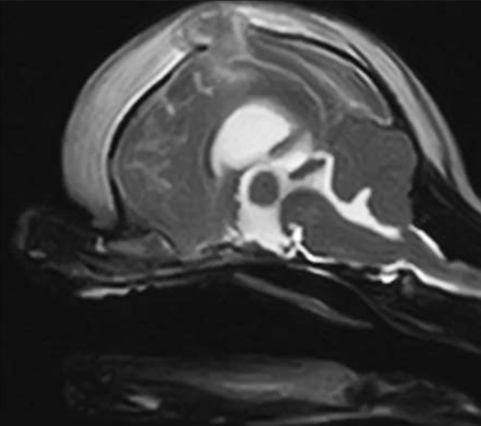

Regarding MRI of dogs with head trauma:

Yanai, H., Tapia-Nieto, R. & Cherubini, G.B. (2015) Results of magnetic resonance imaging performed within 48 hours after head trauma in dogs and association with outcome: 18 cases (2007–2012). Journal of the American Veterinary Medical Association 246, 1222–1229